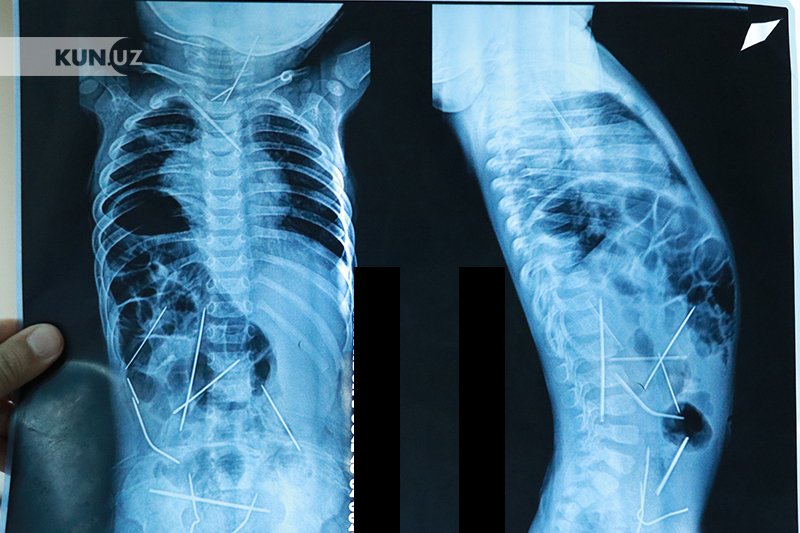

Танасидан 16та игна топилган чақалоқ тирик. Вазирлик расмий хабар берди

Танасидан 16та игна топилиб, кейинги ҳафтада катта шов-шувларга сабаб бўлган фарғоналик 11 ойли чақалоқ айни вақтда тирик. Бу ҳақда Соғлиқни сақлаш вазирлиги «Kun.uz»га маълум қилди.

Эслатиб ўтамиз, аввалроқ Фарғона вилоятида истиқомат қилаётган ёш оиланинг 11 ойли чақалоғи танасидан 16 дона игна топилгани хабар берилганди. Республика шошилинч тиббий ёрдам илмий марказига келтирилган бола тезкорлик билан жарроҳлик столига ётқизилган. Игналардан 13 таси олиб ташланган. Бу пўлат жисмлар гўдак танасида 2 ой муқаддам пайдо бўлганлиги аниқланган. Таъкидланишича, барча игналар танада турлича жойлашган: уларни чақалоқнинг йўғон ичак қисмида, сийдик қопи, кўкрак қафасида, боланинг бўйин қисмида, умуртқа поғонасида, юрак остида топилган. Шифокорларнинг фикрича, 11 ойли чақалоқ ҳеч қачон бунча кўп металлни ютиб юбориши мумкин эмас, қолаверса, қизилўнгач ва ошқозонда ҳеч қандай йиртиқ аломати топилмаган. Биргина фаразни илгари суриш мумкин, игналар тана ташқарисидан, онгли равишда терига тиқилган.